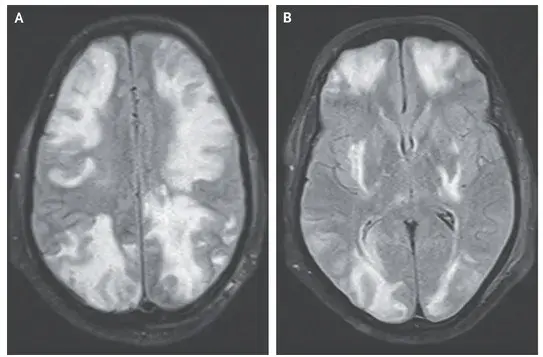

La resonancia magnética (RM) cerebral ponderada en T2 mostró una señal hiperintensa en la sustancia blanca cortical y subcortical, hallazgos consistentes con **edema vasogénico** (imágenes A y B). Los hallazgos de la angiografía por RM arterial y venosa fueron normales.

Se hizo el diagnóstico de síndrome de encefalopatía posterior reversible (PRES) debido al **uso de ciclosporina.**

**Consejos importantes**: A pesar del nombre del síndrome, el PRES no afecta solo las partes posteriores del cerebro. No olvides que puede estar asociado a la **hipertensión**, la **encefalopatía urémica, la eclampsia** o la **terapia inmunosupresora**, como fue el caso de este paciente.

Se retiró el medicamento (ciclosporina) y los síntomas del paciente y los hallazgos de la resonancia magnética se resolvieron (Imagen C).